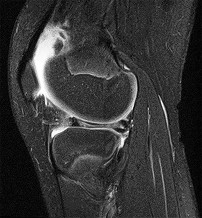

A 22-year-old female soccer player undergoes primary anterior cruciate ligament (ACL) reconstruction using a bone-patellar tendon-bone autograft. Postoperatively, she experiences loss of terminal extension and anterior knee pain. An MRI indicates graft impingement against the intercondylar roof. Which of the following technical errors during tunnel preparation is the most common cause of this specific impingement pattern?

Correct Answer: Tibial tunnel placed too anteriorly

Explanation:

Placing the tibial tunnel too anteriorly is the most common cause of intercondylar roof impingement. The tibial tunnel should be placed posterior to the intersection of Blumensaat's line and the tibial plateau when the knee is in full extension. If placed anterior to this line, the graft will impinge on the notch roof during terminal extension, leading to a loss of extension and potential graft failure.